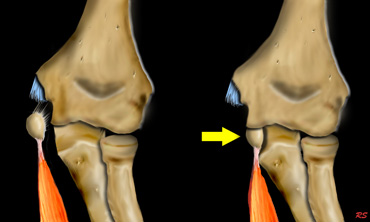

Injury to the elbow joint is usely the result of hyperextension or extreme valgus due to a fall on the outstretched arm.

Scroll through the images on the left to see how hyperextension leads to a supracondylar fracture.

The hemarthros will result in a displacement of the anterior fat pad upwards and the posterior fat backwards.

Extreme valgus

The other important fracture mechanism is extreme valgus of the elbow.

The normal elbow already has a valgus positioning.

When a child falls on the outstrechted arm, this can lead to extreme valgus.

On the lateral side this can result in a dislocation or a fracture of the radius with or without involvement of the olecranon.

When the forces have more effect on the humerus, the extreme valgus will result in a fracture of the lateral condyle.

On the medial side the valgus force can lead to avulsion of the medial epicondyle.

Sometimes the medial epicondyl becomes trapped within the joint.

Because of the valgus position of the normal elbow an avulsion of the lateral epicondyle will be uncommon.